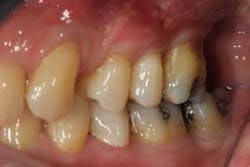

Figures 2a and 2b: Initial presentation in 2011 of the upper right and left molar area, showing advanced bone loss with furcation involvement on the molars.

At presentation, Martin was in his fifties with a medical history significant for controlled hypertension with no known food or drug allergies. He had been lackadaisical with his dental care in the past because of his busy schedule, but he was motivated to get his hygiene and treatment under control. He denied a history of smoking/alcohol/drug use. Based on his full-mouth series (figure 1) and clinical presentation, Martin had generalized, moderate bone loss with localized, severe bone loss in the posterior maxillary right and left quadrants (figures 2a and 2b) as well as the mandibular anterior incisor area (figure 3).